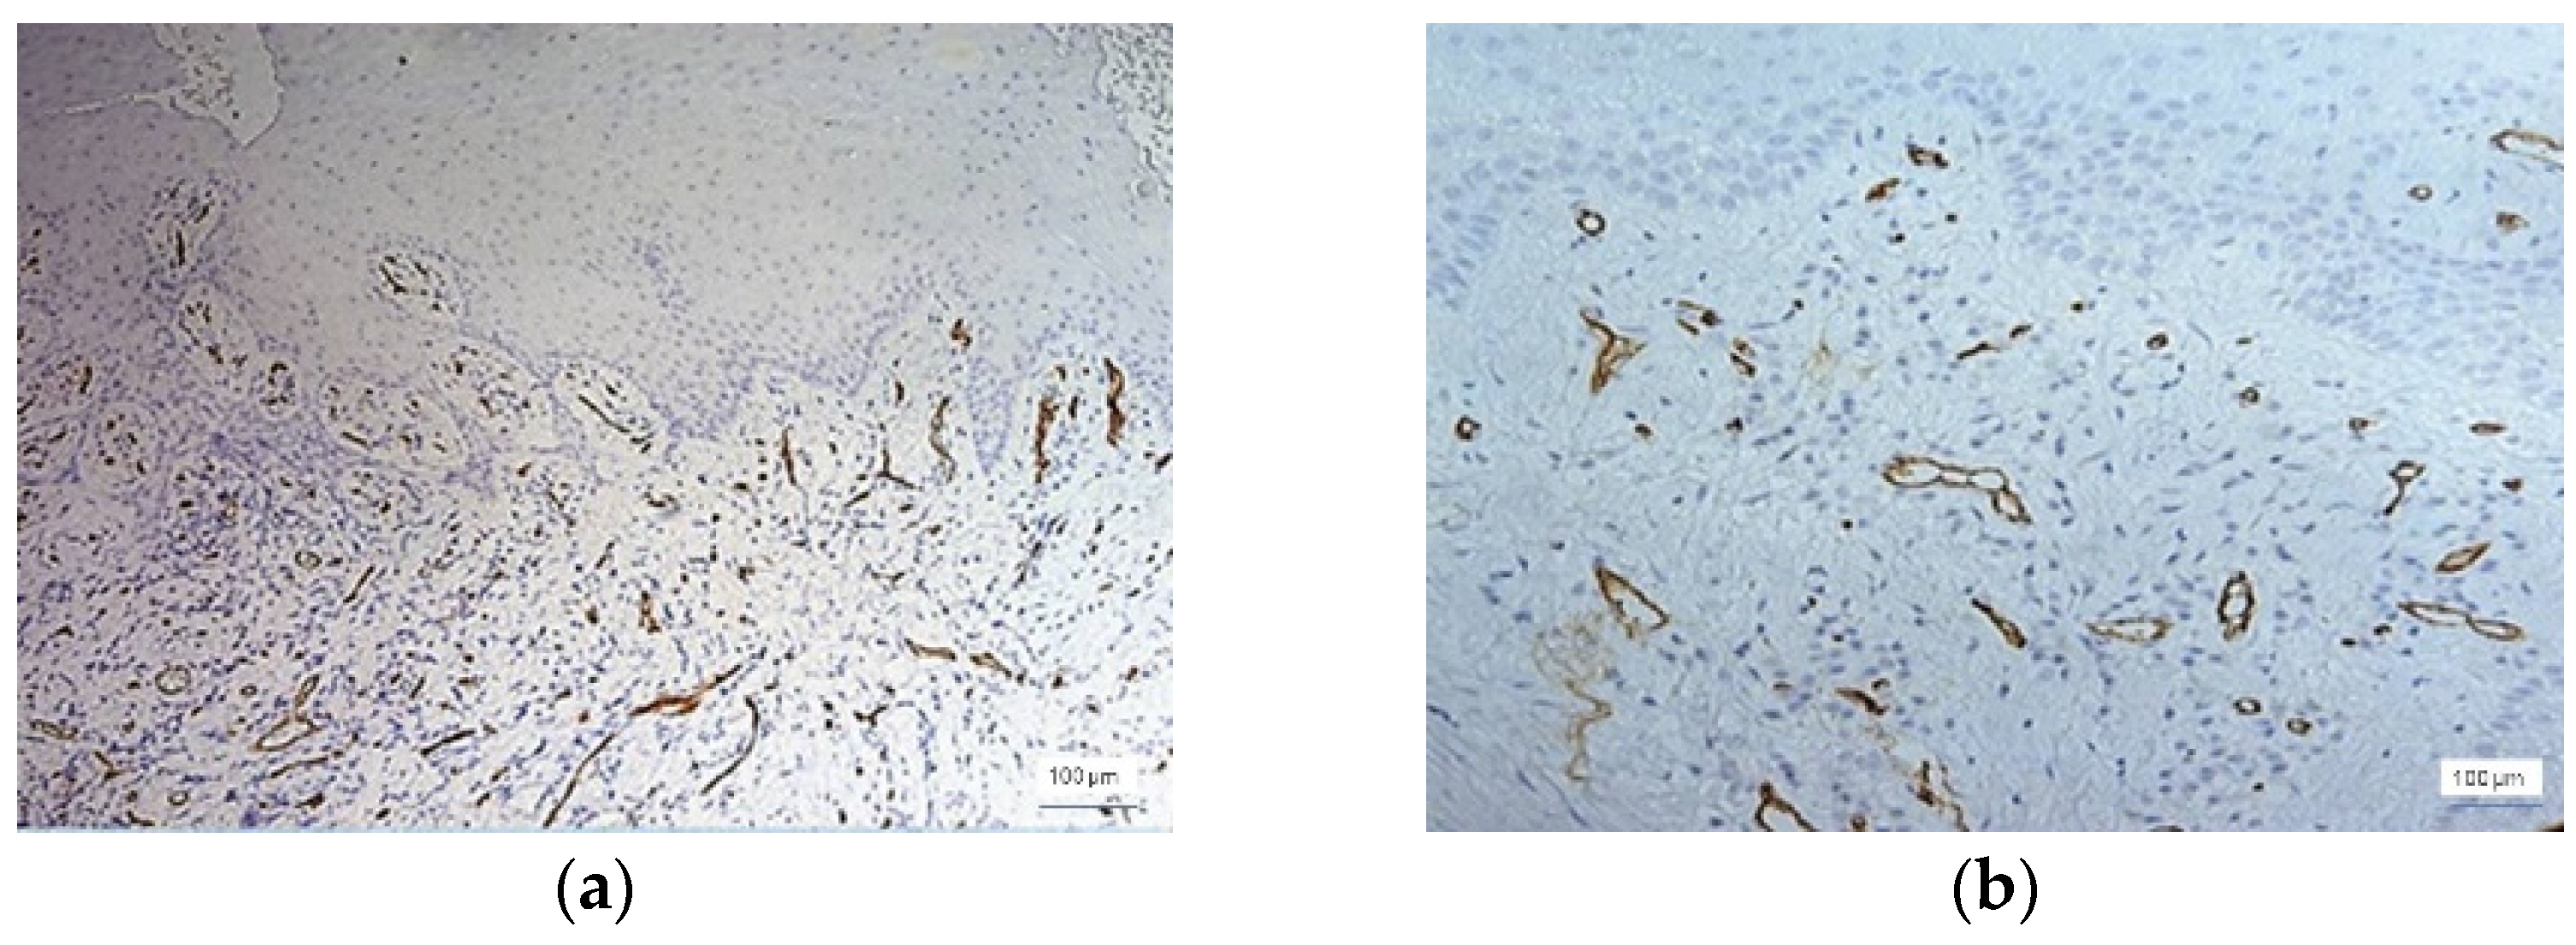

Out of the 39 cases with inflammatory lesions, 15 cases showed mild inflammation (G I = 1, score value 1), 16 cases showed moderate inflammation (GI = 2, score value 2), and 8 cases had severe inflammatory lesions (GI = 3, score value 3), as found by clinical examination. The microscopic features of the normal gingiva, mild, moderate, and severe periodontal disease are shown in Figure 2. CD34 + vessels with a normal morphological appearance were observed in all 12 cases of healthy gingiva. The identified vessels are predominantly capillary and distributed throughout the gingival lamina, including the papillae to the proximity of the surface epithelium. In all of these cases, the blood vessels were small in diameter and all had a lumen. In cases of inflammatory lesions, the morphology of the blood vessels showed changes in accordance with the evolution of the periodontal lesions. Thus, both small-caliber vessels with a very narrow lumen delimited by proliferative endothelial cells and small vessels without a lumen were observed (Figure 3).

Figure 6. Moderate inflammation, GI = 2, and increased microvessel density at the stromal level, ×100: (a) stromal vascular polymorphism and intussusception, ×200, and (b) anti-CD34 immunohistochemical staining and DAB chromogen.

In moderate inflammation, MVD was slightly increased compared to the cases with mild inflammation. The number of vessels was 15–49/field, with the majority being identified in the stroma around the inflammatory infiltrate (Figure 6).